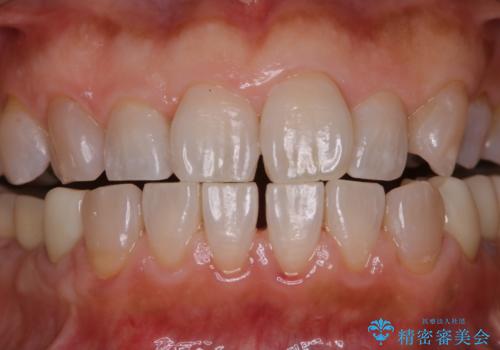

着色・ステイン除去をPMTCで

担当医 歯科衛生士